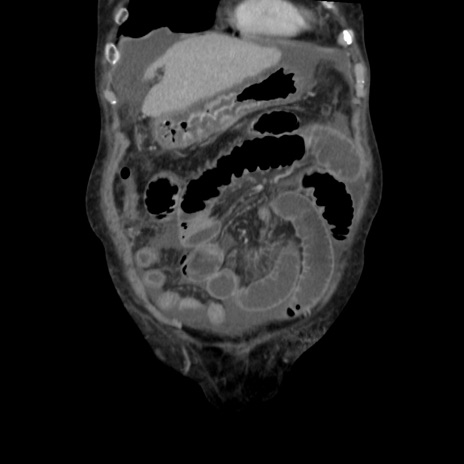

症例31(冠状断像)

【症例】80歳代 女性

【主訴】腹部膨満感

【現病歴】他院にて肝硬変にてフォロー中。1週間前から便秘、腹部膨満感、臍部腫瘤あり受診となる。

【既往歴】肝硬変

【身体所見】腹部膨隆あり、皮膚変化なし、疼痛なし。

【データ】WBC 4600、CRP 0.25